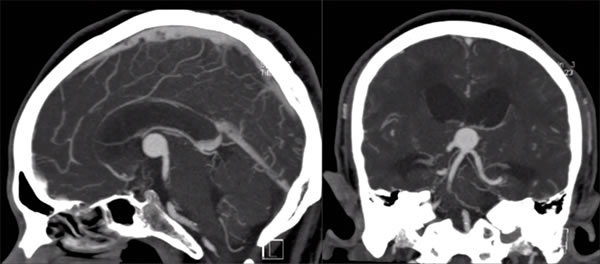

ნეიროვიზუალიზაცია წარმოადგენს კოლოიდური კისტების დიაგნოსტიკის ქვაკუთხედს. ამ კისტებს აქვთ დამახასიათებელი ნიშნები როგორც კტ-ზე, ასევე მრტ-ზე, რაც ჩვეულებრივ სანდო დიაგნოზის დასმის საშუალებას იძლევა.

- კომპიუტერული ტომოგრაფია (კტ): არაკონტრასტულ კტ სკანირებაზე, კოლოიდური კისტები ტიპიურად ჩნდებიან, როგორც კარგად შემოსაზღვრული, მრგვალი ან ოვალური მასები, რომლებიც მდებარეობს კლასიკურ პოზიციაზე წინა მესამე პარკუჭში მონროს ხვრელებთან. ისინი დამახასიათებლად ჰიპერდენსიურია (უფრო ნათელი ჩანს ვიდრე მიმდებარე ტვინის ქსოვილი) შემთხვევების დაახლოებით ორ მესამედში მათი მაღალი ცილოვანი და ქოლესტერინის შემცველობის გამო [1]. დანარჩენ მესამედში ისინი შეიძლება იყოს იზოდენსიური ან, იშვიათად, ჰიპოდენსიური ტვინთან მიმართებაში. კალციფიკაცია კისტის შიგნით იშვიათია. კონტრასტის შეყვანის შემდეგ, ჩვეულებრივ არ აღინიშნება თავად კისტის მნიშვნელოვანი კონტრასტირება, თუმცა ზოგჯერ ჩანს გადაადგილებული სისხლძარღვოვანი წნულის ან შეკუმშული კაფსულის თხელი, სუსტი რგოლოვანი კონტრასტირება. კტ ადვილად ავლენს ასოცირებული ჰიდროცეფალიის (გვერდითი პარკუჭების გადიდების) არსებობასა და ხარისხს.

კლასიკური ლოკალიზაციის (შუა ხაზი, წინა მესამე პარკუჭის სახურავი მონროს ხვრელებთან), ტიპიური ჰიპერდენსიურობის არაკონტრასტულ კტ-ზე, მრტ-ზე დამახასიათებელი სიგნალის ინტენსივობების (ხშირად T1 ნათელი, T2 მუქი/ცვალებადი, არაკონტრასტირებადი, დიფუზიის შეზღუდვის გარეშე) და ასოცირებული ჰიდროცეფალიის არსებობის კომბინაცია, როგორც წესი, კოლოიდური კისტის მაღალი სანდოობის რადიოლოგიური დიაგნოზის დასმის საშუალებას იძლევა.